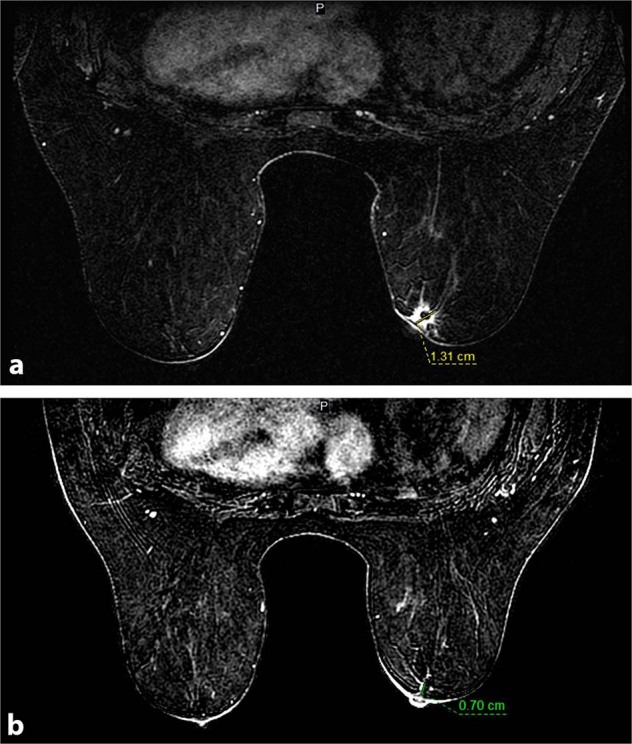

Fig. 1. Pre and post neoadjuvant chemotherapy imaging.

a Pre-therapy MRI showing retroareolar, irregular enhancing mass, 1.3 cm; b Post-therapy MRI showing faint linear enhancement, 0.7 cm.

Physical examination revealed a palpable right breast mass measuring approximately 10 mm immediately deep to the nipple, focally inseparable from the skin. There was no obvious palpable adenopathy. Breast MRI revealed a 13 × 13 × 12 mm irregular enhancing mass with T2 hyperintensity in the retroareolar region along with an abnormal right level 1 axillary lymph node, measuring 10 mm (Fig. 1). As per protocol, the initial core biopsy was reviewed by the MSK Pathology Department. Microscopically, multiple tissue cores were involved by an infiltrating basaloid carcinoma with solid nests and focal cribriform architecture within a desmoplastic stroma showing approximately 5–10% stromal tumor infiltrating lymphocytes (Fig. 2). The neoplastic cells displayed a high nuclear to cytoplasmic ratio, moderate nuclear atypia and conspicuous mitoses. Immunohistochemistry (IHC) demonstrated diffuse expression of cytokeratin 7 (CK7), CK8/18, CK5/6 and c-kit (CD117), occasional p63 reactivity, and MYB nuclear expression (Fig. 2). A MYB translocation was identified by fluorescence in situ hybridization (FISH) utilizing break apart probes. The tumor lacked estrogen receptor (ER), progesterone receptor (PR) and human epidermal growth factor receptor-2 (HER2) expression. The Ki67 proliferation index was approximately 40% (Fig. 2). The histologic, IHC and molecular findings supported a diagnosis of SB-AdCC. Focal in situ carcinoma was also identified. Fine needle aspiration (FNA) of the suspicious right axillary node yielded malignant cells, consistent with metastatic carcinoma.

Breast conservation surgery (BCS) and mastectomy, along with sentinel lymph node biopsy were discussed with the patient. Due to the central location of the tumor and imaging suggesting involvement of areolar skin, a wide excision would also require removal of the nipple areolar complex. In this context, a medical oncology consultation was obtained. Given the triple negative phenotype and biopsy proven positive lymph node status, neoadjuvant chemotherapy was recommended because if it could provide a complete pathologic response in the axilla that would obviate the need for axillary dissection. The patient elected to have an attempt at BCS and thus was given pre-operative dose-dense AC-T (doxorubicin plus cyclophosphamide each two weeks with G-CSF support for four cycles followed by carboplatin each 3 weeks for four cycles plus twelve cycles of weekly paclitaxel), which was well tolerated. Because AdCC is often regarded to be a chemotherapy-resistant subtype of breast cancer the patient was monitored with monthly imaging studies to assess response and ensure there was continued shrinkage of disease. After FDA approval, she was also started on pembrolizumab. However, she developed immune-mediated nephritis after the second dose of pembrolizumab resulting in its discontinuation. An MRI was performed following completion of therapy which showed very faint, residual 7 mm linear enhancement extending towards the nipple, significantly decreased from prior study (Fig. 1). On pre-surgical physical examination, the palpable mass was no longer appreciated, the areolar skin did not feel tethered to the underlying breast tissue and there was no axillary adenopathy. The patient underwent breast conserving surgery with removal of nipple and sentinel lymph node biopsy upon completion of neoadjuvant treatment.